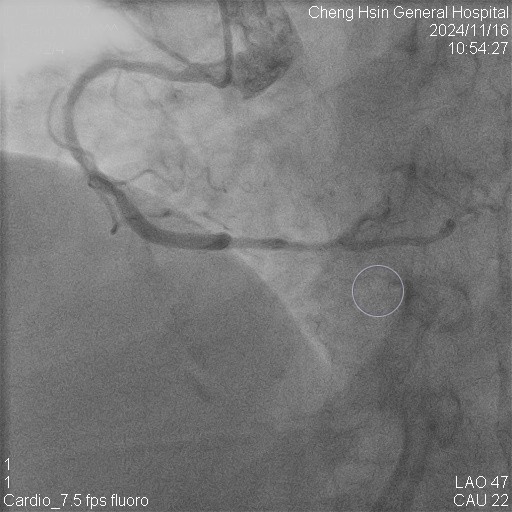

The RCA was calcified but no significantly severe stenosis.The LCX was calcified with mild stenotic lesion and a patent old stent.The LAD was severely calcified with an under-expanded old stent at middle to distal part. The lesion was also severely stenotic. The proximal to middle LAD had moderately stenotic lesion with calcification also.

Initially, we tried to insert IVUS catheter but unable to cross the lesion. We tried a NC balloon but unable to cross it also.Hence, we used rotational atherectomy with 1.5mm burr. However, the burr was unable to cross lesion even in high speed and entrapped in the stent.We removed the burr in guide extension catheter then the NC balloon could cross the lesion. The IVUS cather could also cross it with guide extension catheter support. The stent was almost not expanded. We tried NC balloon high pressure dilation but balloon slippage and burst. The lesion was still un-dilatable. We insert cutting balloon which avoided slippage but remained burst. We escalated the burr size to 1.75mm. The larger burr was not stucked but still unable to cross lesion. Besides, the larger burr causing slow blood flow. After adenosine injection, the patient's blood flow recovered. We reduced the burred size to 1.25mm which cross the lesion once but entrapped while doing polishment. After burr retrieval, we used NC balloon high pressure dilation. The balloon bursted but the lesion remained un-dilatable.Finally, the lithotrypsy balloon could cross the lesion and eliminate 80 pulses. The lesion was expanded much well. The IVUS showed the old stent was expanded and calcium was cracked. We deployed a new stent for old one destruction and proximal dissection. The final IVUS image showed epansion and apposition were accpetable.

The best way to deal with such kind of lesion is prevention. To use intravascular image guidance is very important in complex PCI. Do not insert stent if insufficient lesion preparation. Uncrossable, thick calcium and nodules, limit the efficacy of lithotripsy balloon and often causing IVL balloon rupture. Before inserting the lithotripsy balloon, we might need rotational atherectomy to modified the lesion or the road to the lesion. Larger burr size makes slow flow while smaller one let you stuck in such kind of stent jacket calcium tunnel.The Rotatripsy had demonstrated effectiveness and safety in addressing severe calcified coronary artery disease.